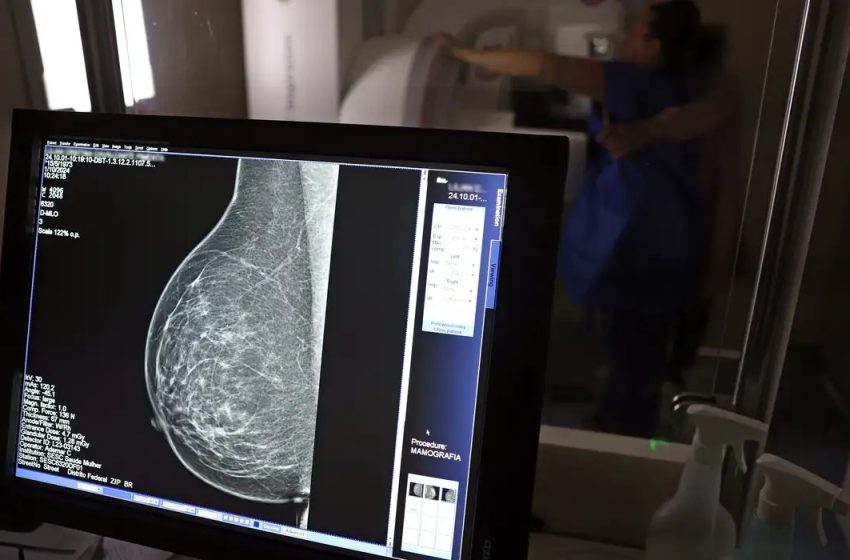

© José Cruz/Agência Brasil

Uma nova lei, publicada nessa segunda-feira (6), reforça o direito do trabalhador com contrato via Consolidação das Leis do Trabalho (CLT) de se afastar até três dias por ano para realizar exames preventivos de câncer, sem desconto salarial.

O direito já estava incluído na CLT desde 2018. A partir de agora, as empresas passam a ser obrigadas a divulgar essa informação, além de outras relacionadas a campanhas oficiais de vacinação contra o HPV e sobre o acesso a serviços de diagnósticos de cânceres de mama, próstata e de colo do útero.

O texto estende o uso das folgas também para a realização de exames preventivos do HPV, além dos de câncer que já estavam previstos na legislação anterior. A a Lei 15.377 foi sancionada pelo presidente Luiz Inácio Lula da Silva, e publicada na edição do Diário Oficial da União (DOU).